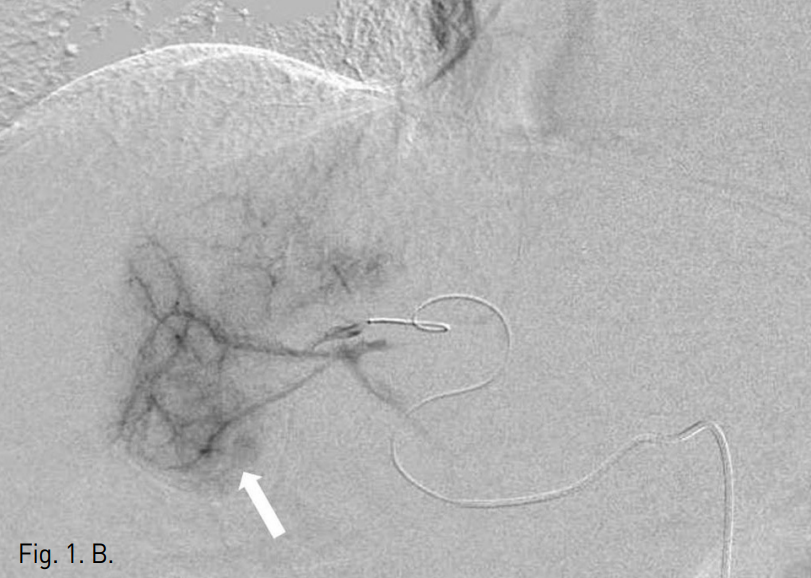

종괴의 외측과 하측이 담낭과 인접해 있어 RFA시 열손상의 가능성이 있어 PEIT needle (Hakko, Japan)을 삽입하고 총 13cc의 absolute ethanol을 주입하여 PEIT를 시행하였다.

Fig. 2

A. Sonography before PEIT procedure demonstrates the adherence of the gallbladder (arrow) to the S4 HCC (arrow head).

B. Sonographic image taken after PEIT of the S4 HCC. Total 13cc absolute ethanol has been injected at both lateral and inferior aspect of the mass with the remnant portion measured as 1.5x1.8cm (arrow).

C. Sonography during the RFA ablation of the remnant tumor. RFA probe with 2cm ablation tip was used.